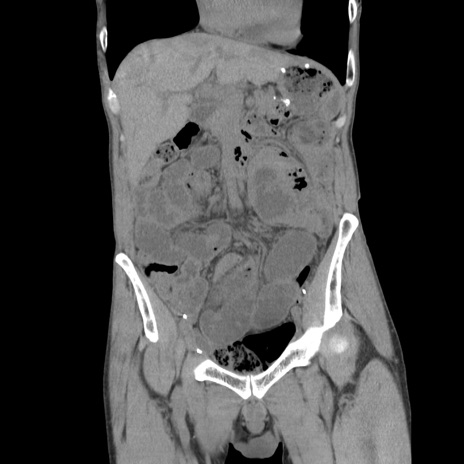

症例11(冠状断像)

【症例】 60歳代男性

【主訴】 下腹部痛

【現病歴】 本日夜中より下腹部痛の症状認め、受診。

【既往歴】 膀胱癌(膀胱全摘+尿管皮膚瘻術) 、胃癌術後

【身体所見】 BT 35.3℃、PR 58/min、BP 136/98mHg、腹部平坦、軟、腸蠕動音±、ストマ留置あり、左上腹部~正中部に圧痛あり、反跳痛なし。

【データ】WBC 5100、CRP0.01